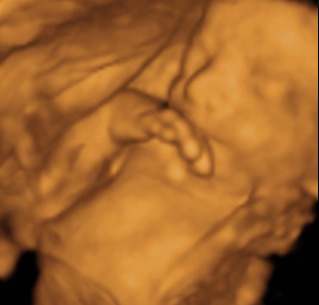

POcak fotó: mi itthon csináltunk, az is tökjó lett. Én ugye lenni kisbálna, így nem akartam volna művészi képeket csinálni magamról... Most se kívánkozik

Igaz Alex pocakról nincsen annyi képem, mint Hannáról... most valahogy Hanna és a meló elvitte azt a maradék erőmet is, hogy a képeket megcsináltassam Ádámmal. Szimplán nem jutott eszembe.